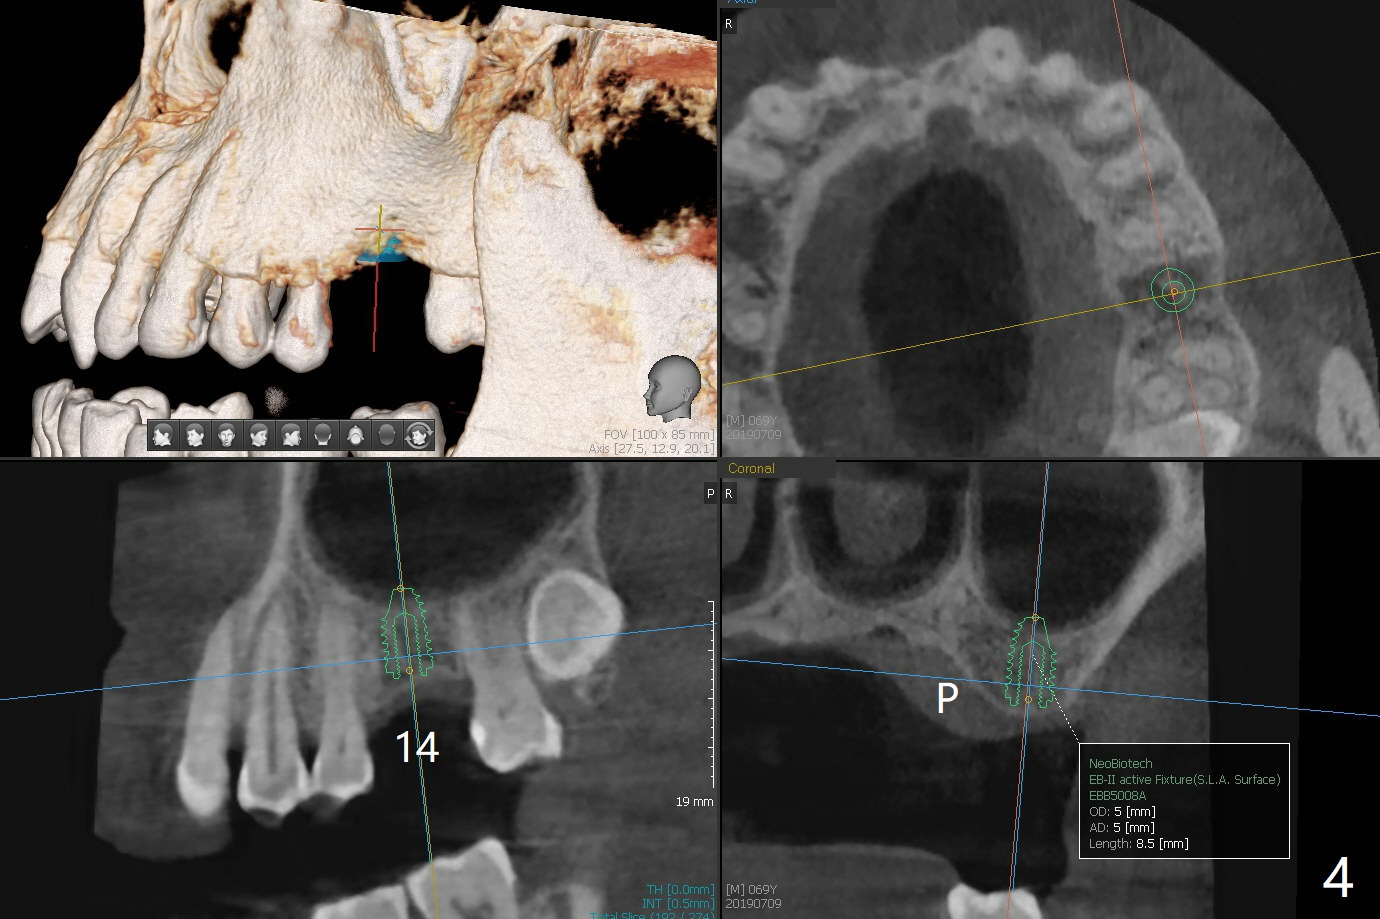

A 69-year-old man (ex-soldier) had the tooth #8 extracted for a flipper nearly 8 years earlier (Fig.1 (obliterated canal)). A denture tooth is added at #14 after extraction in NY a few years later (Fig.2). In spite of sufficient bone width at #8, a 2.5x10 mm mini implant will be chosen to reduce the chance of palatal thread exposure (Fig.3 P). A 5x8.5 mm implant will be placed at #14 to achieve enough stability and not cause sinus complication (Fig.4). Take preop photos to show the anterior deep overbite and overjet. In fact the patient canceled the surgery. Two years later, he returns with history of right TMJ dislocation, which may be related to reduced mastication efficiency and partial edentulism (Fig.5,6).